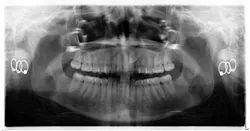

When a full permanent dentition is present (with the exception of impacted canines), the labial/palatal position of the canine will have an influence on what the provider can do. (1) Arguably, obtaining a CBCT is considered mandatory and will allow for a more inclusive treatment plan creation. If angulation is favorable, then consideration to remove the primary canine and wait six months to see if there is movement of the permanent canine is an option. If extraction of the canine(s) is needed, then a premolar substitution, which is dependent on occlusion, can be used in the space. An implant can also be an appropriate alternative. When pulling a canine into the occlusal arch, there is risk involved. Trauma to adjacent teeth (root resorption) and ankylosis are some of the most common complications.The patient was put in full orthodontics and referred to a surgeon for extraction of the primary canines, exposure, and placement of retention on the impacted canines to pull them directly down from their current position.

A ballista appliance was used to prevent a facial pull of the canines in order to avoid and prevent resorption of the roots of the lateral incisors. As movement progressed over the course of the next year, eruption of the canines was considered a success. Once in position, they will be pulled facially into occlusion.

The patient is pleased with the progress reached thus far and is ecstatic at the anticipation of a successful outcome.